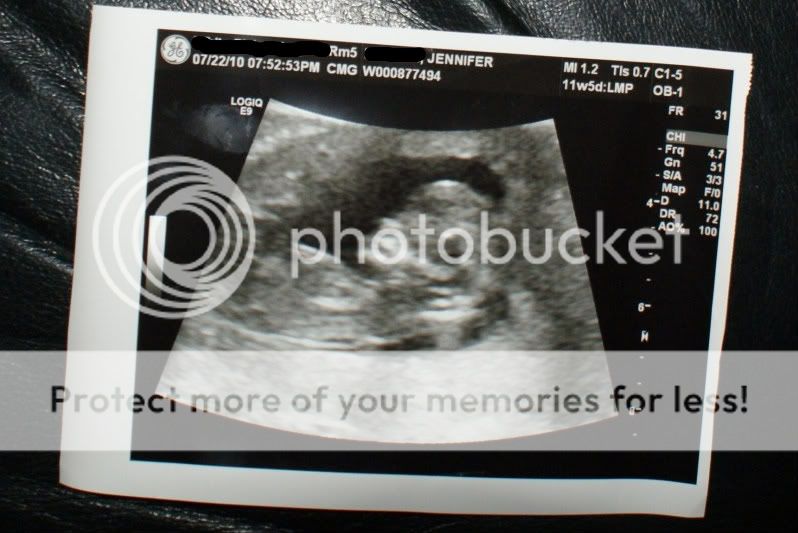

11W5D

11 wks and 5 days